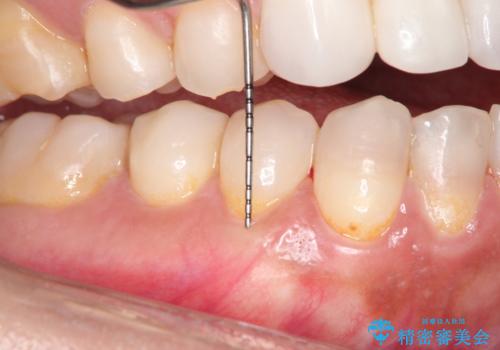

- 昔に受けた矯正治療がきっかけで歯肉が下がってしまった事を主訴として来院された患者様です。

結合組織移植術を行う方法を提案しましたが、傷口が口蓋にもできるのが嫌だとのことで、代替案としてバイオマテリアルを併用した根面被覆術を計画致しました。

治療対象部位は右下4,5,6番の3本です。